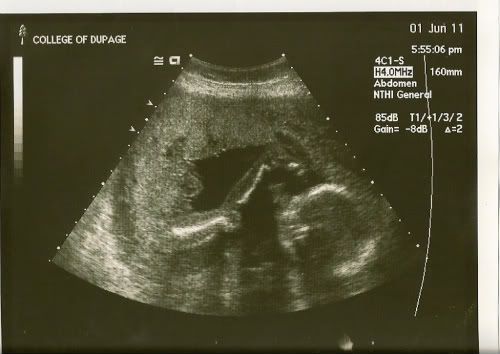

AFM -- I got a couple u/s pics uploaded from last week. Here's a profile pic with her hand in front of her face. She had just taken her thumb out of her mouth.

Image

And here's one where she was playing with her toes. It was so cute and amazing to watch her do that! I'm sooo in love.

Lou - I never got around to voting, but mine was for Chloe. Beautiful name! LOVE the u/s pics!!! What an animated little girl she is!

Lou- she is amazing! the photo almost made me cry (of course that is true of just about anything right now). I can't believe how perfect she looks. What a blessing.

Lou - Love the pics of your little one! Soooo cute!

Lou- Love the ultraosund pics they came out so good. I picked those two names out but Chris vetoed them. We don't know the sex and wont till August 3rd. If we have a girl he really wants to name her Sophia aftre his Grandmother. But his cousin did that so not sure what to do.